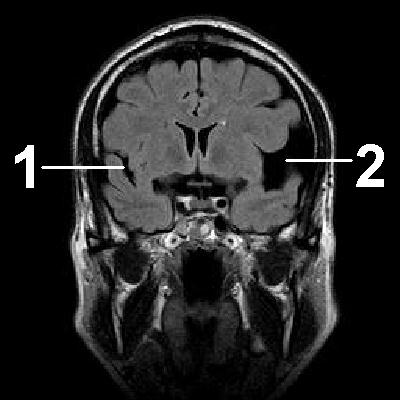

Диагностика заключается в проведении КТ или МРТ.

По результатам этих исследований можно точно установить наличие кисты, ее размеры и местоположение.

Арахноидальная киста головного мозга. Заполненное цереброспинальной жидкостью образование, располагающееся между дупликатурой арахноидальной оболочки. Может иметь врожденную и вторичную природу. Зачастую протекает латентно, без клинических проявлений. При увеличении объема киста дебютирует симптомами внутричерепной гипертензии, судорожными пароксизмами и очаговым неврологическим дефицитом. Диагностируется в основном по данным МРТ головного мозга. При нарастании клинических симптомов требуется хирургическое лечение — дренирование кисты, ее фенестрация, иссечение или шунтирование.

Клиника арахноидальной кисты не имеет специфичных проявлений и соответствует клинической картине, общей для большинства объемных образований головного мозга. К последним относятся внутримозговые и оболочечные гематомы, первичные и метастатические опухоли мозга, абсцесс головного мозга, внутримозговая киста. Осмотр невролога и первичное неврологическое обследование (электроэнцефалография, реоэнцефалография и эхо-энцефалография) позволяют установить наличие интракраниального образования с внутричерепной гипертензией и существующую судорожную активность головного мозга. Для уточнения характера объемного образования и его локализации необходимо проведение МРТ, СКТ головного мозга или КТ.

Оптимальным диагностическим методом для распознавания арахноидальных кист выступает МРТ головного мозга с контрастированием. Использование контрастных веществ позволяет отдифференцировать кисту от опухоли головного мозга. Основным критерием арахноидальной кисты, отличающим ее от опухоли, является отсутствие способности накапливать контраст. При помощи МРТ проводится дифференциальная диагностика с субдуральной гематомой, субарахноидальным кровоизлиянием, субдуральной гигромой, абсцессом, инсультом, энцефалитом и тд церебральными заболеваниями.